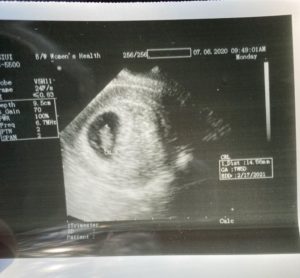

I found out I was pregnant 3 weeks after the surgery!

I am currently 9weeks and 6 days! Many more ultrasounds to come 🙂